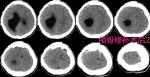

青年重癥顱腦外傷患者術(shù)后恢復(fù)良好一例經(jīng)驗(yàn) 關(guān)鍵疾?。?a href="http://m.akellydesign.com/tags/so/創(chuàng)傷性硬膜外血腫(右側(cè)額顳部),創(chuàng)傷性硬膜下血腫(左額顳)-4-1.html" target="_blank">創(chuàng)傷性硬膜外血腫(右側(cè)額顳部),創(chuàng)傷性硬膜下血腫(左額顳) 現(xiàn)病史【一般資料】 男性,26歲,農(nóng)民 【主訴】 車禍傷后昏迷不醒約50分鐘。 【現(xiàn)病史】患者約于50分鐘前乘坐手扶拖拉機(jī)與汽車發(fā)生車禍,傷后立即昏迷,伴鼻腔流血,無(wú)肢體抽搐,無(wú)大小便失禁,院外未做診治,120接入我院急診科,辦理綠色通道入院,行顱腦CT檢查結(jié)果示“1.雙側(cè)額顳頂硬膜下血腫并積氣;2.雙側(cè)額顳葉腦挫裂傷;3.多發(fā)顱面骨骨折并顱內(nèi)積氣?!保燹D(zhuǎn)入我科?;颊邆蠡杳裕催M(jìn)食水,未解大小便。 【既往史】既往有“腦積水、內(nèi)斜視手術(shù)”史。否認(rèn)“高血壓、心臟病、糖尿病”病史。否認(rèn)“肝炎、結(jié)核”...